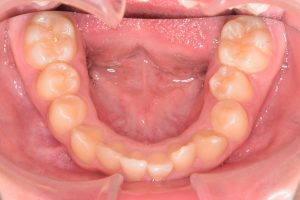

2期治療開始時(2023年7月)と装置撤去時(2025年9月)の写真です。

下あご

・下顎前歯部叢生

・非抜歯で配列

・下顎前歯部IPR